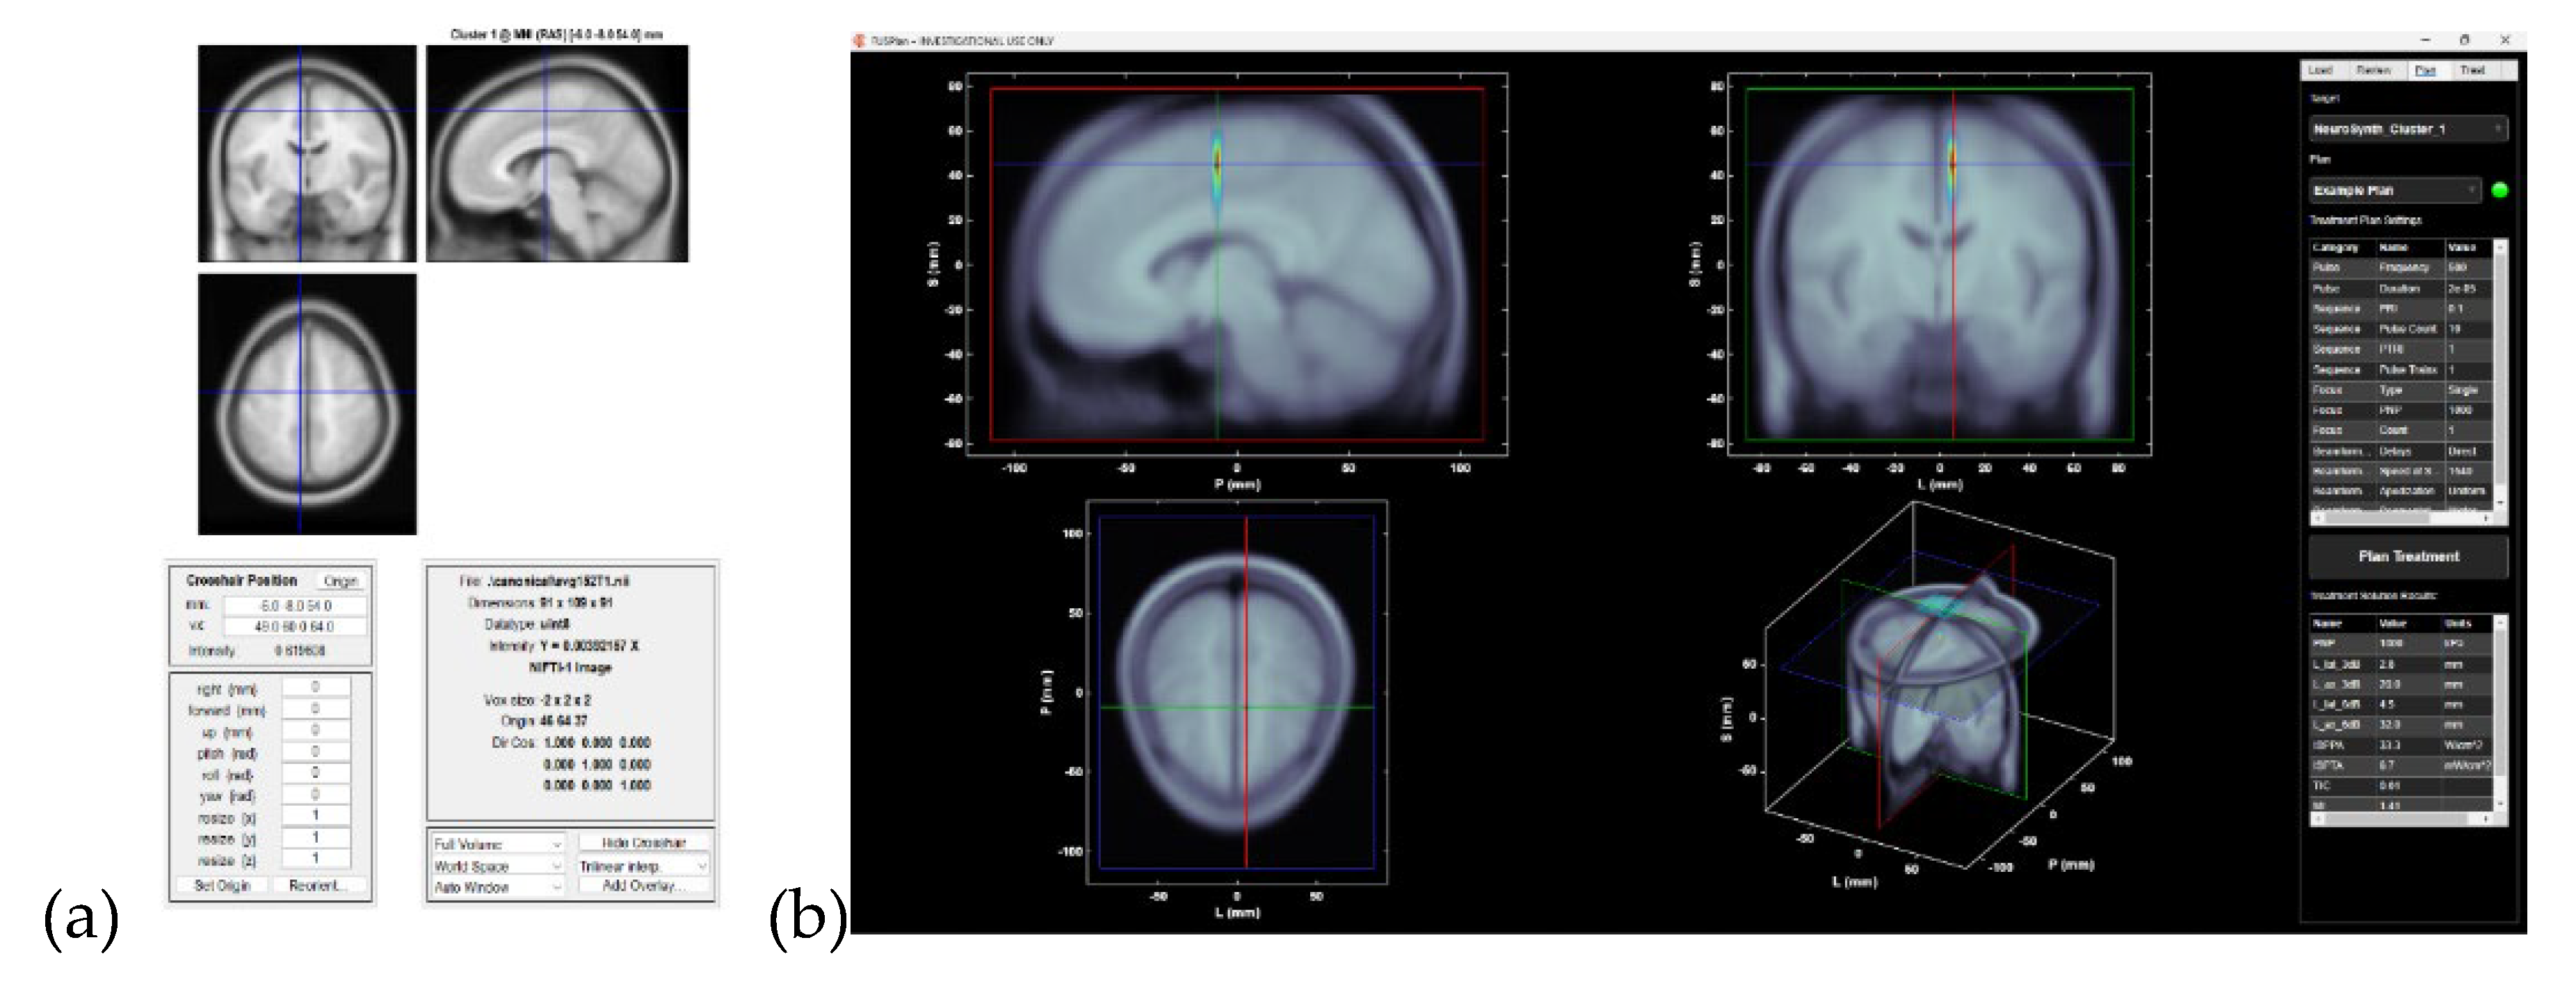

05 September 2025

3. Meta-Analysis By Linking Neurosynth Studies To Subnetworks To Guide Ultrasond Neuromodulation